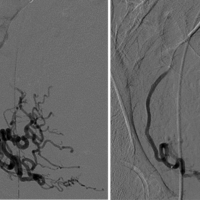

During UFE, a catheter is inserted through a blood vessel in the groin or arm and guided by X-ray images to the blood vessels that feed the fibroids of the uterus. Tiny particles are then injected to stop blood flow to the fibroids. Once blood flow to the fibroids is blocked, patients return home while the fibroids shrink gradually over the next weeks and months.

During the procedure a tiny catheter is precisely guided from an artery in the wrist or inguinal region until it reaches the superior rectal artery branches of the inferior mesenteric artery, which supplies blood to the hemorrhoids. Once the catheter is in position, embolic agents, such as small particles or coils, are injected into the artery to block the blood flow to the hemorrhoids. By blocking the blood supply to the hemorrhoidal tissue, the hemorrhoids shrink and eventually resolve. The procedure is typically performed under moderate sedation with the patient asleep. This procedure is generally considered a safe and effective treatment option for symptomatic hemorrhoids, offering a shorter recovery time and potentially fewer complications compared to traditional surgery.